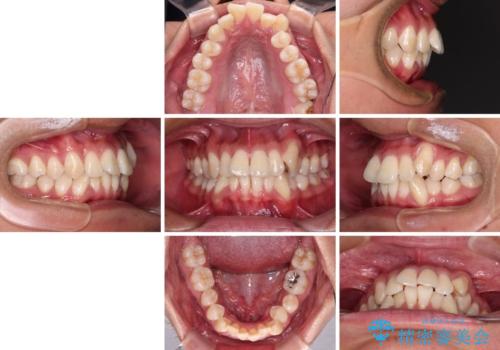

補助装置を併用してスムーズに インビザラインによる矯正治療

- 八重歯と飛び出している前歯を気にして来院された患者様です。

歯列としてはインビザラインでもワイヤー矯正でも対応できるものでしたが、上顎の八重歯や下顎小臼歯の捻転といったインビザラインでは時間のかかってしまう歯列不正が認められたため、補助装置やワイヤー矯正を治療当初に使用することで、インビザラインによる治療をスムーズに行えるように計画しました。

インビザラインは得意・不得意の差がはっきりとしているため、ワイヤー装置などをうまく活用することで、治療期間を短縮するとともに、より理想的な仕上がりを達成することができます。